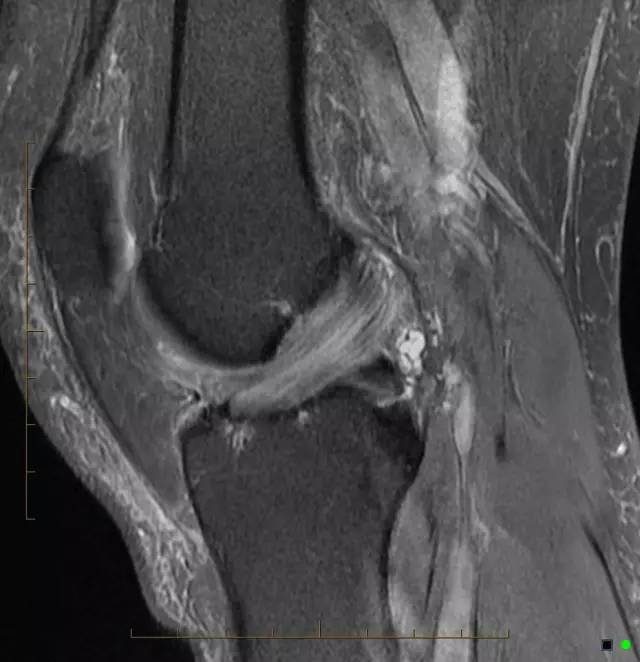

芹菜杆征是膝关节前交叉韧带黏液样变性的特征性影像表现。当前交叉韧带增粗肿大,有一定紧张度,在质子加权和T2WI的矢状位上表现为边界模糊呈高信号改变,而前交叉韧带纤维束则呈低信号条状影散布于高信号区内,形成类似芹菜杆的一种征象。

正常前交叉韧带(ACL)是由胶原纤维组成的,并在磁共振成像表现为低信号带。芹菜杆征(celery stalk sign)为ACL黏液样变性的特征性表现。关节镜下所见黏液样变性为淡黄色硬化物质,当ACL黏液样变性时,无定形的黏液细胞增加ACL的信号强度,并局部地分布于完整的、平行走行的ACL纤维束,形成了芹菜杆样外观。